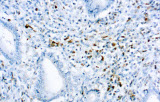

- Assegnazione del lignaggio & principali diagnosi differenziali: Fenotipizzazione cellule B vs cellule T (es. CD20 vs CD3), supportata da fattori di trascrizione nucleari delle cellule B come PAX5 quando i marcatori pan-B sono deboli/assenti.

- Linfoma a cellule mantellari: ciclina D1 e SOX11 come marcatori chiave, incluso supporto per i casi ciclina D1 negativi.